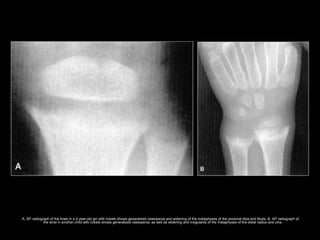

• The M/C radiologic sign is generalized

osteopenia.

• Increased lucency, widening, elongation,

irregularity, and cupping of the metaphyses.

– Earliest; Slight axial widening of the physis

– Next; Increased lucency of the zone of provisional

calcification.

– More advance; The physis widens and its contour

becomes irregular.

A, AP radiograph of the knee in a 2-year-old girl with rickets shows generalized osteopenia and widening of the metaphyses of the proximal tibia and fibula. B, AP radiograph of

the wrist in another child with rickets shows generalized osteopenia, as well as widening and irregularity of the metaphyses of the distal radius and ulna.